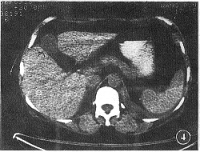

腹腔横断面(通过网膜孔)